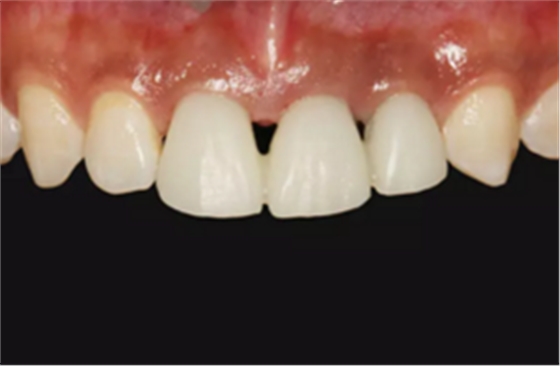

图16 软组织成形后口内像

图25 最终修复后复查口内像